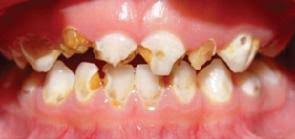

La caries del biberón es un tipo de caries que afecta a los dientes primarios, también llamados dientes de leche de los lactantes y los niños y se caracteriza por ser rápidamente progresiva y muy destructiva.

Afecta principalmente a niños desde el inicio de la erupción dentaria (sobre los 6 meses) hasta los 4 o 5 años.

Los dientes más afectados son los cuatro dientes anteriores superiores ya que los inferiores aunque salen primero están protegidos por la lengua, el labio y glándulas salivales a la hora de amamantar ya sea con pecho o biberón.

La caries rampante se manifiesta por la aparición de pequeñas manchas blanquecinas, indoloras, que a veces no se perciben a tiempo y en un lapso de 3 a 6 meses dejan a los dientes sin esmalte.

Las caries en un principio se aprecian como manchas de color blanco que van haciéndose amarillentas y se van extendiendo y haciendo cada vez más oscuras.

Estas manchas aparecen generalmente en la cara lingual o interna de los incisivos centrales superiores, cerca de la encía.

Van avanzando rodeando el diente como un anillo hasta acabar decapitando al diente, que pierde la corona o parte superior, quedando solo la raíz dentaria.